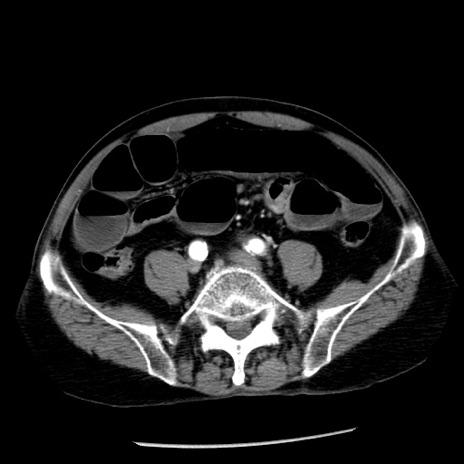

症例26(横断像)

【症例】80歳代男性

【主訴】嘔吐

【現病歴】昨晩2回嘔吐あり、今朝になっても嘔吐あり。来院。

【既往歴】胃潰瘍

【身体所見】意識清明、BT 37.6℃、BP 166/95mmHg、HR 100bpm、SpO2 97%、腹部:平坦・軟、腸蠕動音聴取良好、圧痛なし。

【データ】WBC 21900、CRP 1.46